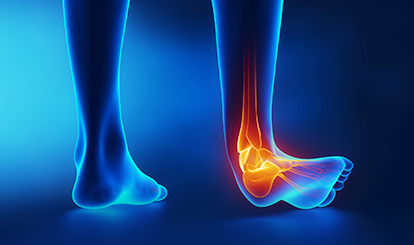

갑작스럽게 또는 만성적으로 통증이 발생하며 발목, 발, 발가락 등 전반적으로 나타납니다.

발목/발바닥의 통증, 부종, 습관적 발목 삠

위 증상 중 한가지라도 해당된다면 “발목관절염”일 수 있습니다.

반복적으로 발목을 사용하거나 과도한 동작으로 연골이 마모되어 나타나는 질환입니다. 주로 나이가 든 노인에게 발병률이 높으나 발목 사용량이 많은 전 연령층에서도 발생할 수 있습니다.